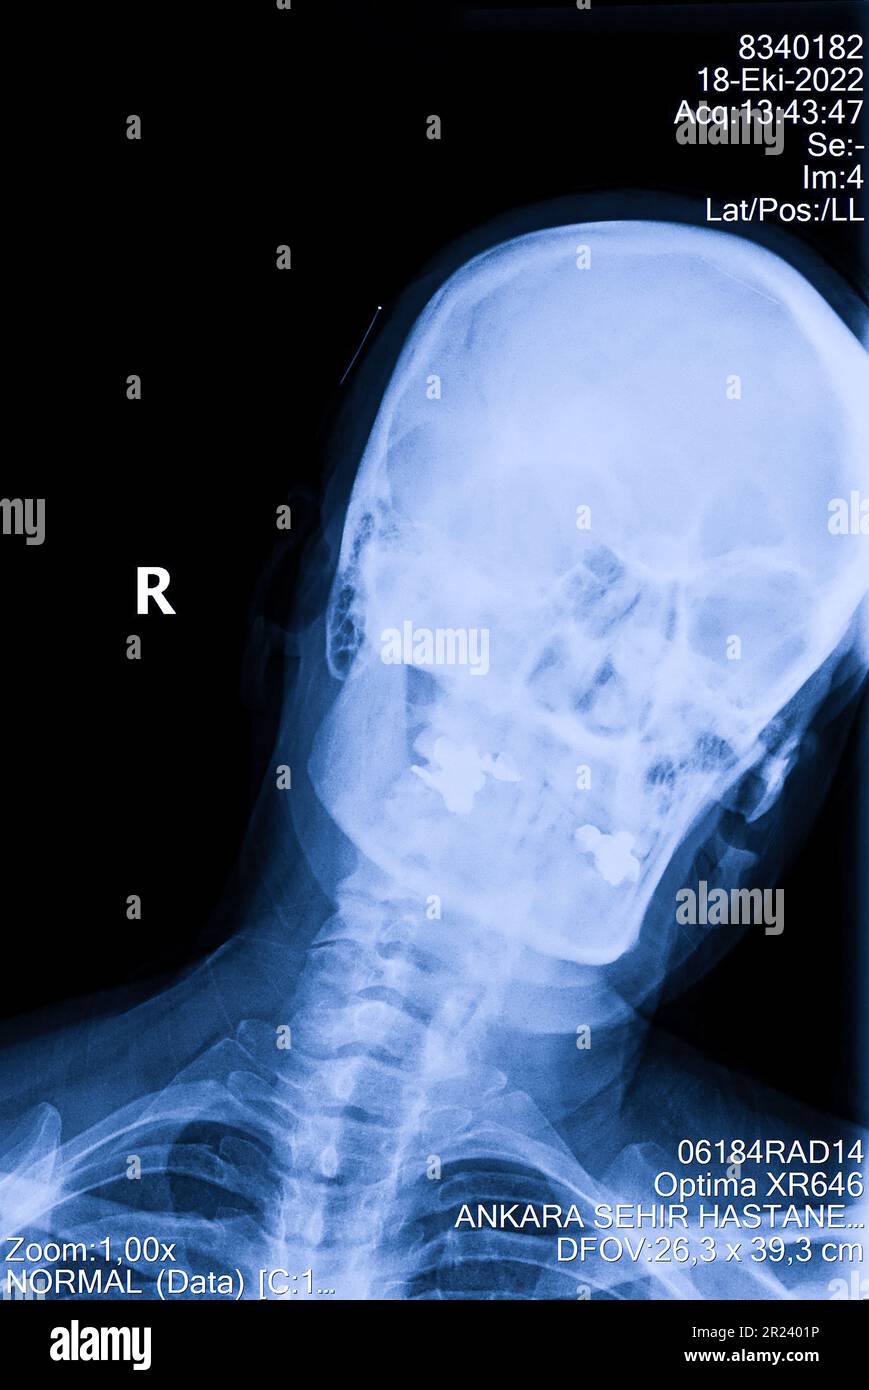

Normal Cervical Spine, XRay Stock Image C039/3917 Science Photo Down Syndrome Cervical X Ray This is no longer true. Lateral cervical radiograph in a female with down syndrome due to chromosomal translocation. When obtaining screening radiographs to detect clinically relevant “instability” in children with down syndrome,. The condition is mostly asymptomatic and. The patient developed progressive gait. Many patients with down syndrome (ds) develop upper cervical spine instability that may lead to spinal cord. Down Syndrome Cervical X Ray.

X ray normal cervical spine Stock Photo 2835193 Alamy Down Syndrome Cervical X Ray This is no longer true. The condition is mostly asymptomatic and. When obtaining screening radiographs to detect clinically relevant “instability” in children with down syndrome,. Lateral cervical radiograph in a female with down syndrome due to chromosomal translocation. Sensitivity, specificity, and positive and negative predictive values of nul and fel radiographs for identifying clinically significant cervical spine. Many patients with. Down Syndrome Cervical X Ray.